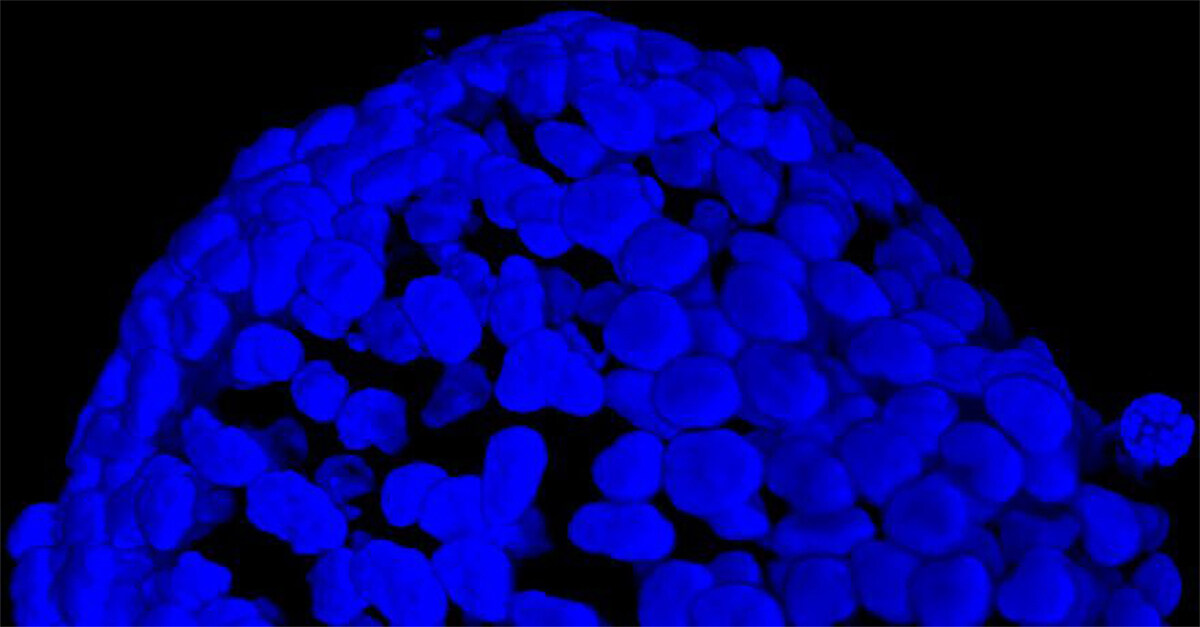

我们采用 CrestOptics X-Light V3 转盘共聚焦结合 Prime BSI 相机(Photometrics,像素尺寸 6.5 um)进行采集。我们比较了使用 20 倍空气物镜(CFI Plan Apo Lambda,尼康,0.7 NA 和 1mm WD)和 25 倍硅油物镜(CFI Plan Apo Lambda S,尼康,1.05 NA 和 0.55 mm WD)进行的采集。在图 A 中,我们展示了从总共 150 um 的 Z 堆栈中获得的最大强度投影 (MIP) 图像;特别是,使用 20 倍空气物镜和 25 倍硅油物镜获得了相同的球体。图 B 显示了使用两种物镜获得的 3D 球体同一区域的放大。

图 A:使用 20 倍空气物镜(顶部)和 25 倍硅油物镜(底部)获得的肿瘤球体 Z 堆栈的最大密度投影 (MIP)。活细胞用钙黄绿素(绿色)标记,死细胞用 PI(红色)标记。细胞核用 Hoechst(蓝色)染色。比例尺:100 um。这些图像是使用 CrestOptics X-Light V3 转盘获取的。